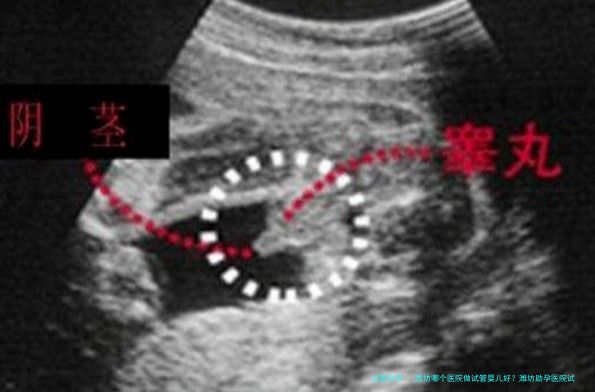

试管婴儿的术前检查,是夫妻两人都须要实现的,检查的缘由主要是为了筛查试管婴儿助孕或反复流产的缘故,评估夫妇二人的生育力,筛查夫妻二人的健康状况,确定女方身体是否合适妊娠等。